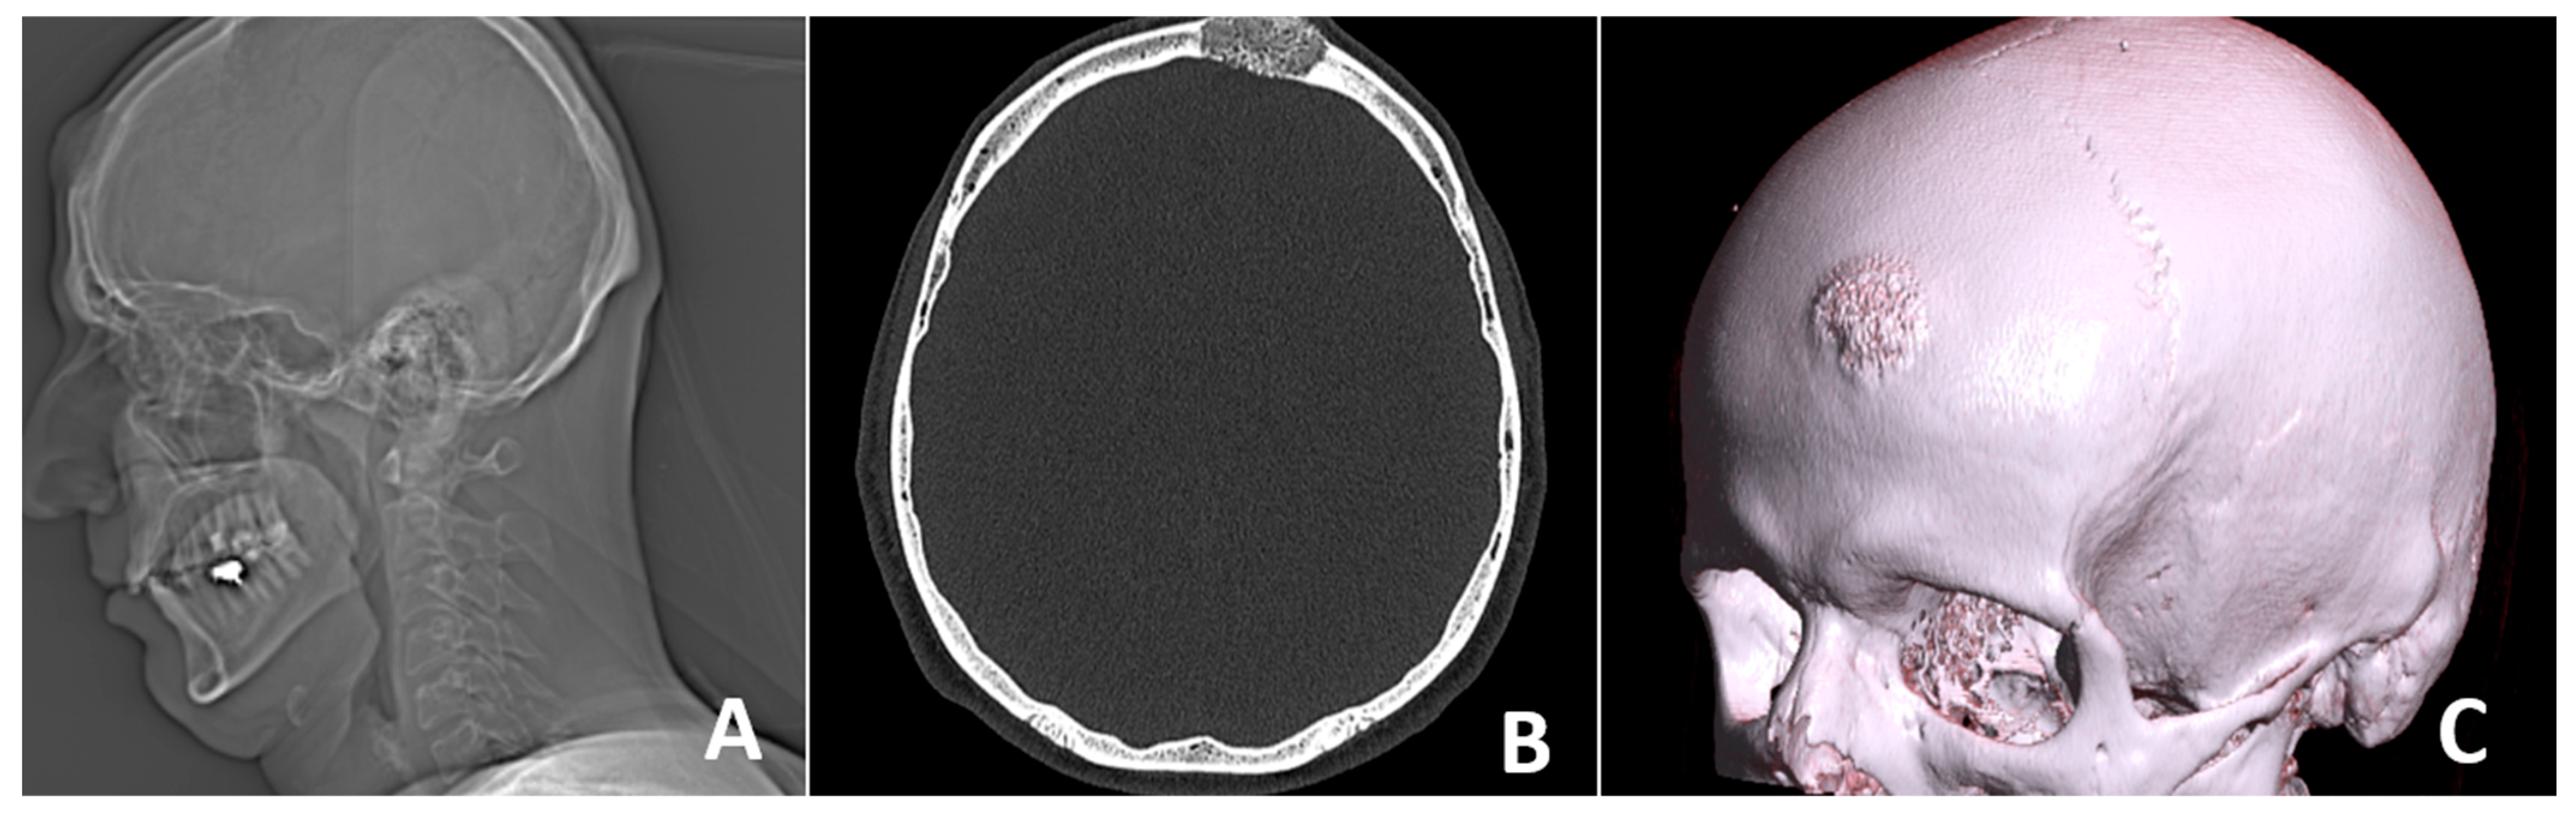

CT scan of the head—native (non-contrast) conditions was performed one day after surgery, showing normal density characteristics and preserved differentiation between white and gray matter in the brain structures. The ventricular system was symmetrical with preserved capacity. Normal position of the midline structures was observed. The posterior cranial fossa was intact, and the subarachnoid spaces were free. Bones—postoperative defect in the left frontal area. No complications were observed, as shown in Figure 7.

At the 6-month follow-up, the patient demonstrated a sustained long-term result with fully restored calvarial stability, ensuring adequate protection of the underlying brain structures. A follow-up CT scan of the head was performed again, showing normally presented brain structures and complete osteointegration of the iliac crest graft. The cosmetic outcome remained satisfactory, with no contour irregularities or visible deformities. No postoperative complications were observed, such as hematoma formation, infection, or extrusion of the bone graft. Overall, the patient maintained excellent functional and aesthetic results, confirming the success of the surgical intervention.

Figure 7. Control (A) X-ray and (B) CT was performed on the following day.